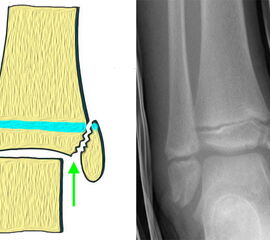

Übergangsfrakturen sind spezielle Verletzungen, die ausschließlich in der Lebensphase beobachtet werden, in welcher die Wachstumsfugen teilweise geschlossen sind. Die Wachstumsfuge an der distalen Tibia schließt sich von ventromedial beginnend nach dorsal und lateral. Während die bereits geschlossene Wachstumsfuge eine hohe Stabilität aufweist, ist der knorpelige Anteil der noch offenen Fuge wesentlich weniger widerstandsfähig. Die mechanisch schwächste Schicht der Wachstumsfuge ist der Blasenknorpel. Durch Biege- und Scherkräfte kommt es zu einer Verletzung der Wachstumsfuge mit Aussprengung eines metaphysären Keils. Übergangsfrakturen sind „unvollendete“ Fugenschaftfrakturen bei welchen die bereits geschlossene Fuge ein Auslaufen der Frakturlinie durch die Fuge verhindert und daher die Bruchlinie ins Gelenk ausläuft (v. Laer 2013).

Rein epiphysäre Frakturen werden als Twoplane-Frakturen bezeichnet. Der Frakturverlauf liegt in der Epiphyse und dem noch nicht verknöcherten Anteil der Wachstumsfuge. Gibt es noch einen zusätzlichen metaphysären Keil handelt es sich um eine Triplane-Fraktur. Bei einer Triplane-Fraktur kann sich in Einzelfällen die metaphysäre Fraktur bis in die Epiphyse fortsetzen, sodass eine zusätzliche Querfraktur resultiert. Es entsteht der Eindruck eines zusätzlichen hinteren Volkmann Fragments.

• Twoplane-Fraktur: Epiphysäre Fraktur, welche epiphysär und durch den noch nicht verknöcherten Teil der Fuge verläuft (Aitken II Verletzung bei einer teilweise mineralisiert Wachstumsfuge).

• Triplane-I-Fraktur: Epiphysäre Fraktur, mit teilweisem Verlauf durch die Wachstumsfuge und gleichzeitigem metaphysären Keil.

• Triplane-II-Fraktur: Epiphysäre Fraktur, mit Verlauf durch die Wachstumsfuge. Der metaphysäre Keil setzt sich in die Epiphyse fort, was zu einer weiteren quer verlaufenden Frakturlinie im Gelenk führt.